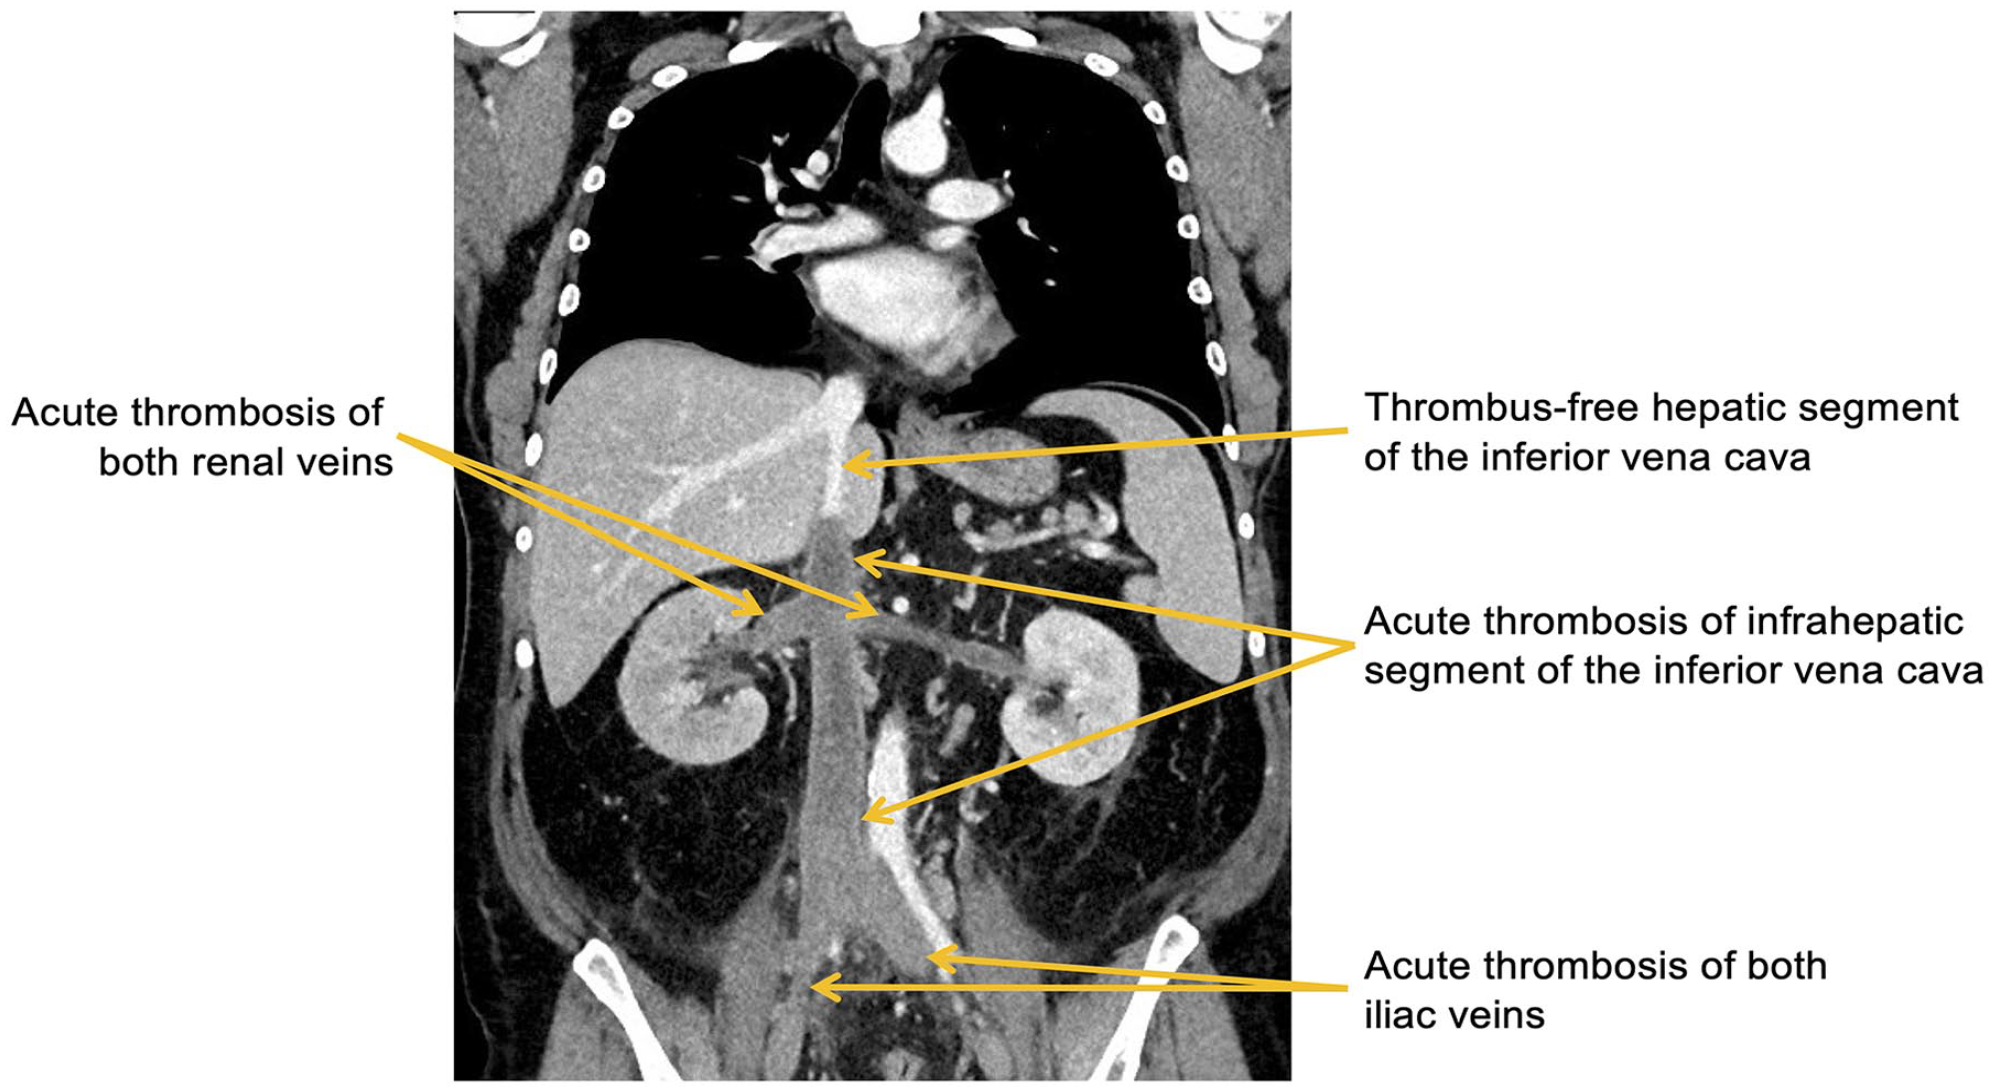

Comprehensive imaging studies by duplex ultrasound of both lower limbs and thoracoabdominal computed tomography showed an acute thrombosis of the infrahepatic inferior vena cava, both renal veins, both iliac veins, as well as both femoral veins (Figure 1). Moreover, a hemorrhagic infarction of the right kidney as a consequence of renal vein thrombosis was found. Both popliteal veins and the intrahepatic segment of the inferior vena cava were free of thrombus.

Thoracoabdominal computed tomography showing acute thrombosis of the infrahepatic inferior vena cava, both renal veins and both iliac veins.